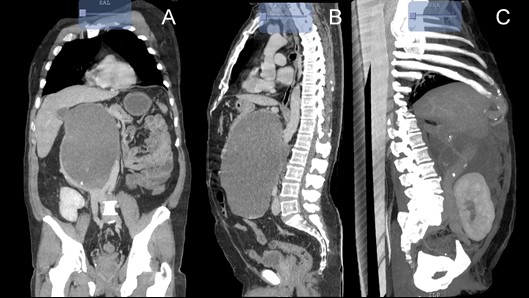

Methodology: We describe the case of a 59-year-old male, group B+, who received a transplant from a Related Living Donor in 2011, sharing a haplotype, undergoing induction with Daclizumab 80mg DU, and with immunosuppression based on Cyclosporine 1.8mg every 12h, Mycophenolate 1g every 12 hours and Prednisone 5 mg every 24 hours; He began suffering in December 2020 with abdominal pain in the epigastrium, hyporexia and weight loss, Laboratories: Creatinine: 1.15, Urea 32, Glucose 102mg / dL, Hb 17.6mg / dL, Hto 52.40, Leukocytes 7.9X1000, Platelets 233x1000; tumor markers: Alpha fetus 2.16 ng/ml, CA 19-9 524.5 IU/ml, A. Carcinoembryonic 67.53 ng/ml. On examination, the kidney graft showed no alterations, and a palpable abdominal tumor of 30 x 25 cm, painful on palpation. Tomography reported a retroperitoneal tumor of 25.8 x 16.9 x 19 cm with displacement of adjacent structures and compression of the inferior vena cava.

Resection of the tumor is performed, finding: Retroperitoneal tumor of 25 x 25 x 20 cm on the vena cava and aorta, which displaces the pancreas towards the head, without its involvement, with a mucous content of 2 Lts.